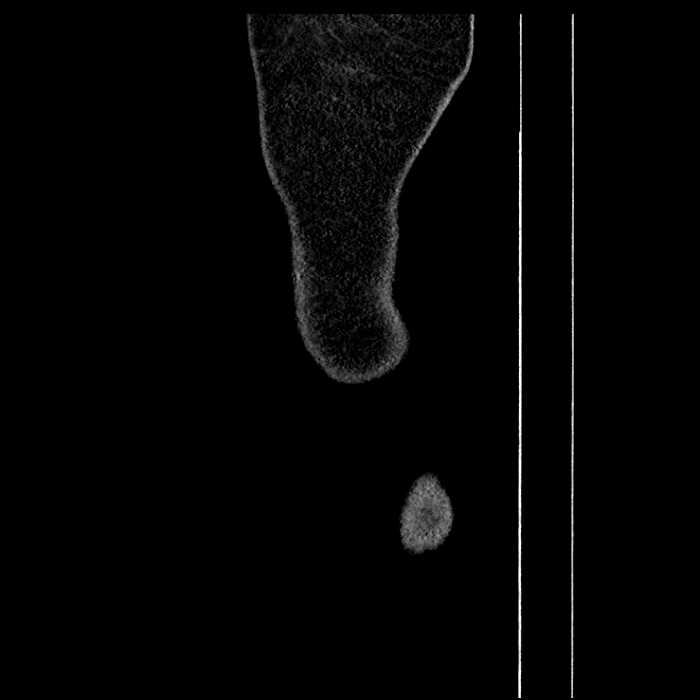

• Mild mural thickening of a segment of the sigmoid colon with adjacent fat stranding and a 1.5 cm fluid and gas collection along the tip of an inflamed diverticulum

• Loss of the normal fat plane between this collection and adjacent loops of small bowel, which demonstrate mural thickening

Acute sigmoid diverticulitis complicated by a small contained perforation and a large abscess in the right hepatic lobe. Additional small subcapsular abscesses along the anterior margin of the left hepatic lobe.

Additionally, loss of the normal fat plane between the peridiverticular collection and adjacent thickened loops of small bowel raises the potential for an enterocolonic fistula.

Hepatic abscess showing the double target sign with low density internally surrounded by a thin inner enhancing rim (red arrow) and ill-defined outer low density rim (yellow arrow). Blue arrow indicates an internal septation. Red arrows: additional smaller subcapsular abscesses. Red arrow: focal contained perforation associated with diverticulitis.